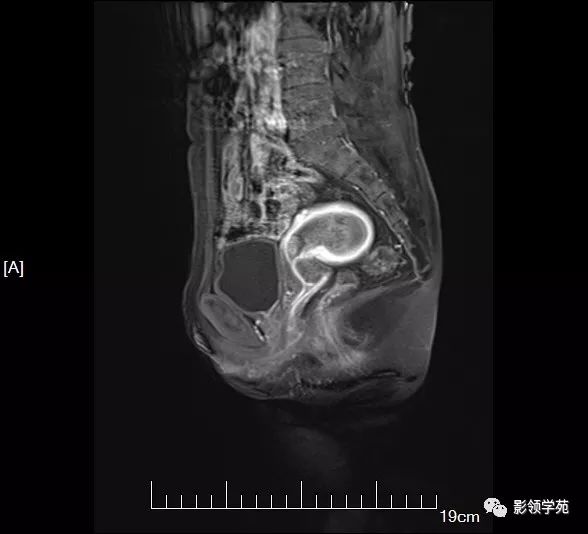

mri7031:子宫占位